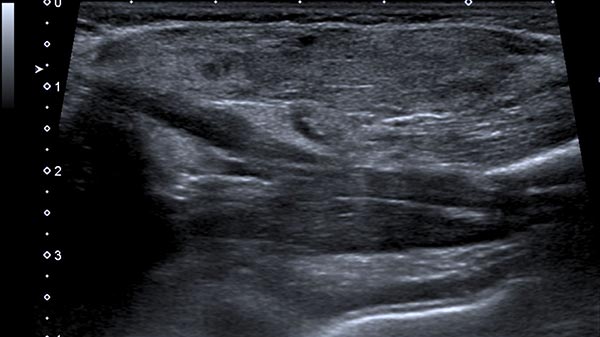

Ab der 2. Lebenswoche waren bei dem Säugling insgesamt 8 kleine kutane infantile Hämangiome typischer Art langsam wachsend an der Haut sichtbar. Zusätzlich eine umschriebene, langsam größer werdende Schwellung ventral in der Mitte des linken Oberarmes. Die darüber liegende Haut war nicht verfärbt. In der hier abgebildeten B-Bild-Sonographie dieser Stelle, im Verlauf Ende des 4. Lebensmonats, zeigt sich ein relativ echoarmer Tumor im Subkutangewebe.

Die entsprechende B-Bildsonographie Ende des 8. Lebensmonats zeigt neben der Volumenzunahme auch deutlich vermehrte echoarme Anteile in dem Tumor. Dies entspricht Zellproliferaten und ist ein Merkmal eines in Proliferation befindlichen infantilen Hämangioms, kann aber auch bei anderen vaskulären Tumoren vorkommen.